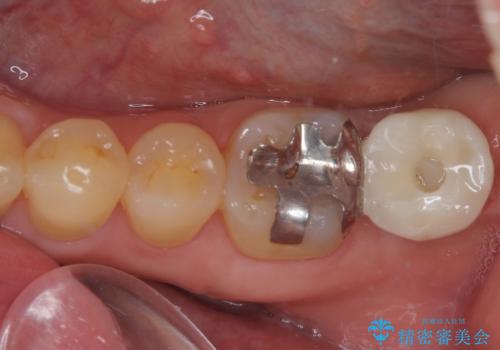

- 奥歯がしみるとのことで来院された患者様です。

診査をしたところ、目視でも明らかな、とても大きなむし歯があありました。

既に治療により詰め物が装着されている歯であったため、オールセラミッククラウンによる補綴治療を選択することとしました。